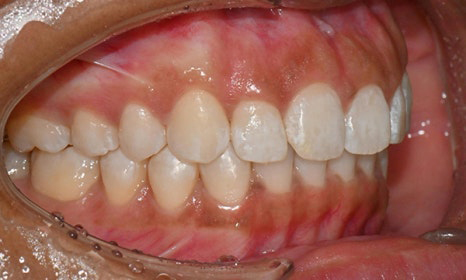

장치 착용 2달 후 사진 (2025.6)

교정을 시작하고 두 달 뒤,

8번째 장치를 착용하고 있을 때 찍은 사진을 보면

치아 배열도 많이 좋아졌고, 공간도 거의 닫혔어요.